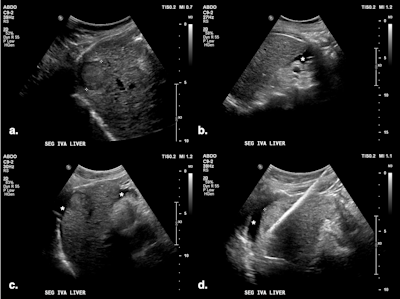

(A) Targeted HCC in segment IV-A near the diaphragm. (B) Artificial ascites (*) created using a 6.3 Fr Dawson-Mueller catheter inserted along the inferior margin of the left hepatic lobe. (C) Satisfactory distribution of ascites beneath the diaphragm. (D) Microwave antenna inserted at the target, with mechanical leveraging performed to further accentuate the gap between the liver and diaphragm.

Di Muzio and colleagues prefer the 6.3 Fr Dawson-Mueller catheter for creating artificial ascites, but alternatives include a 14-20 G Chiba needle, One-Step Centesis Catheter, or a 5 Fr vascular catheter/sheath. They use a 1 L saline bag with a pressure cuff to expedite the infusion process, and the fluid distribution and liver displacement are monitored with ultrasound. There is no consensus on how thick the layer of fluid separating the structures should be, with the literature reporting between 5 and 10 mm.